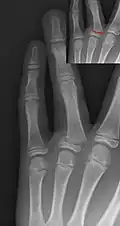

Salter–Harris II fracture of ring finger proximal phalanx. -